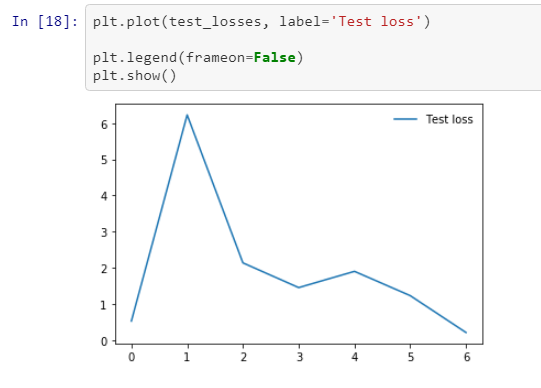

The ResNet-50 model was trained on the train image dataset and validated on the test image dataset, starting initially with 3 epochs which were increased to achieve the threshold of maximal test accuracy and test loss above which the test loss started to increase due to overfitting of the model. The ideal number of epochs found on tuning the model parameters was seven.

Test losses after each epoch were plotted using matplotlib library and are shown in the figure below.